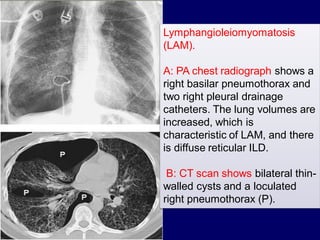

Associated pneumothorax suggests

lymphangioleiomyomatosis or LCH.

Lymphangioleiomyomatosis

(LAM).

A: PA chest radiograph shows a

right basilar pneumothorax and

two right pleural drainage

catheters. The lung volumes are

increased, which is

characteristic of LAM, and there

is diffuse reticular ILD.

B: CT scan shows bilateral thinwalled cysts and a loculated

right pneumothorax (P).